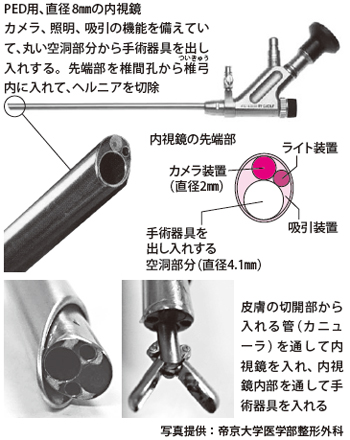

経皮的内視鏡下椎間板ヘルニア摘出術の治療の進め方は?

背骨の中心線より10cmほど外側を6~8mm切開、内視鏡を挿入し、ヘルニアを切除します。患者さんもモニターを見ながら、30~60分。翌朝には退院する1泊2日の手術です。

マーキングした位置に、6~8mmの切開を加え、目標となる椎間板を目がけ、椎間孔を通して一気に直径6~8mmのカニューラと呼ばれる管を差し込みます。このとき、ためらわずにしっかりと奥まで差し込み、固定することを心がけています。これは、PEDを始めた当初、手術後、ヘルニアの圧迫による症状はとれるものの、別の神経症状が出てしまう患者さんがいて、その予防策を検討した結果によるものです。

カニューラを固定したら、そこから内視鏡を挿入します。内視鏡を入れると、その部分の映像が、大きなモニターに映し出されます。内視鏡先端にはカメラ装置に加え、光源から光を送る装置がついているので、明るく鮮明な映像が得られます。

PEDの大きな特徴として、常時、生理食塩水を流しながら手術を進めることが挙げられます。ほかの多くの手術の場合、片手に吸引管を持って血液や、洗浄のために入れた生理食塩水を吸いながら手術を進めますが、PEDやMEDでは内視鏡に吸引装置がついているので、別途、吸引管を持つ必要がありません。PEDでは還流させる水圧により、ほぼ出血はなく、手術の状況に応じて流量は調節します。

ヘルニアの切除は、内視鏡に設けられている筒状の器具操作用の空間から、手術器具を出し入れして行います。用いるのはボール状のドリルや、切除用の鉗子などで、神経をよけながら、ヘルニアを少しずつ慎重に取り除いていきます。